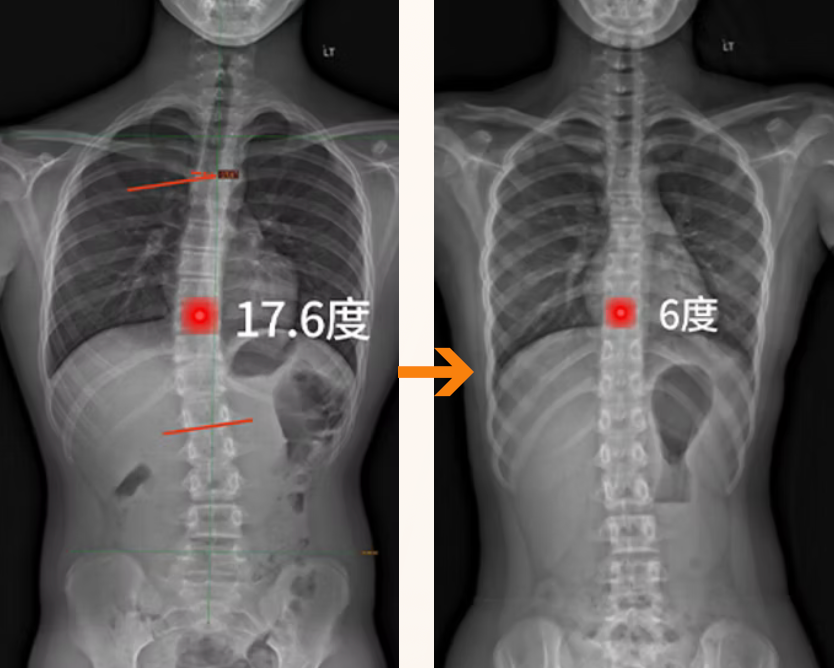

用戶實證改善11.6度

佩戴前:側彎角度 為17.6度

佩戴後:側彎角度 為 6.0度